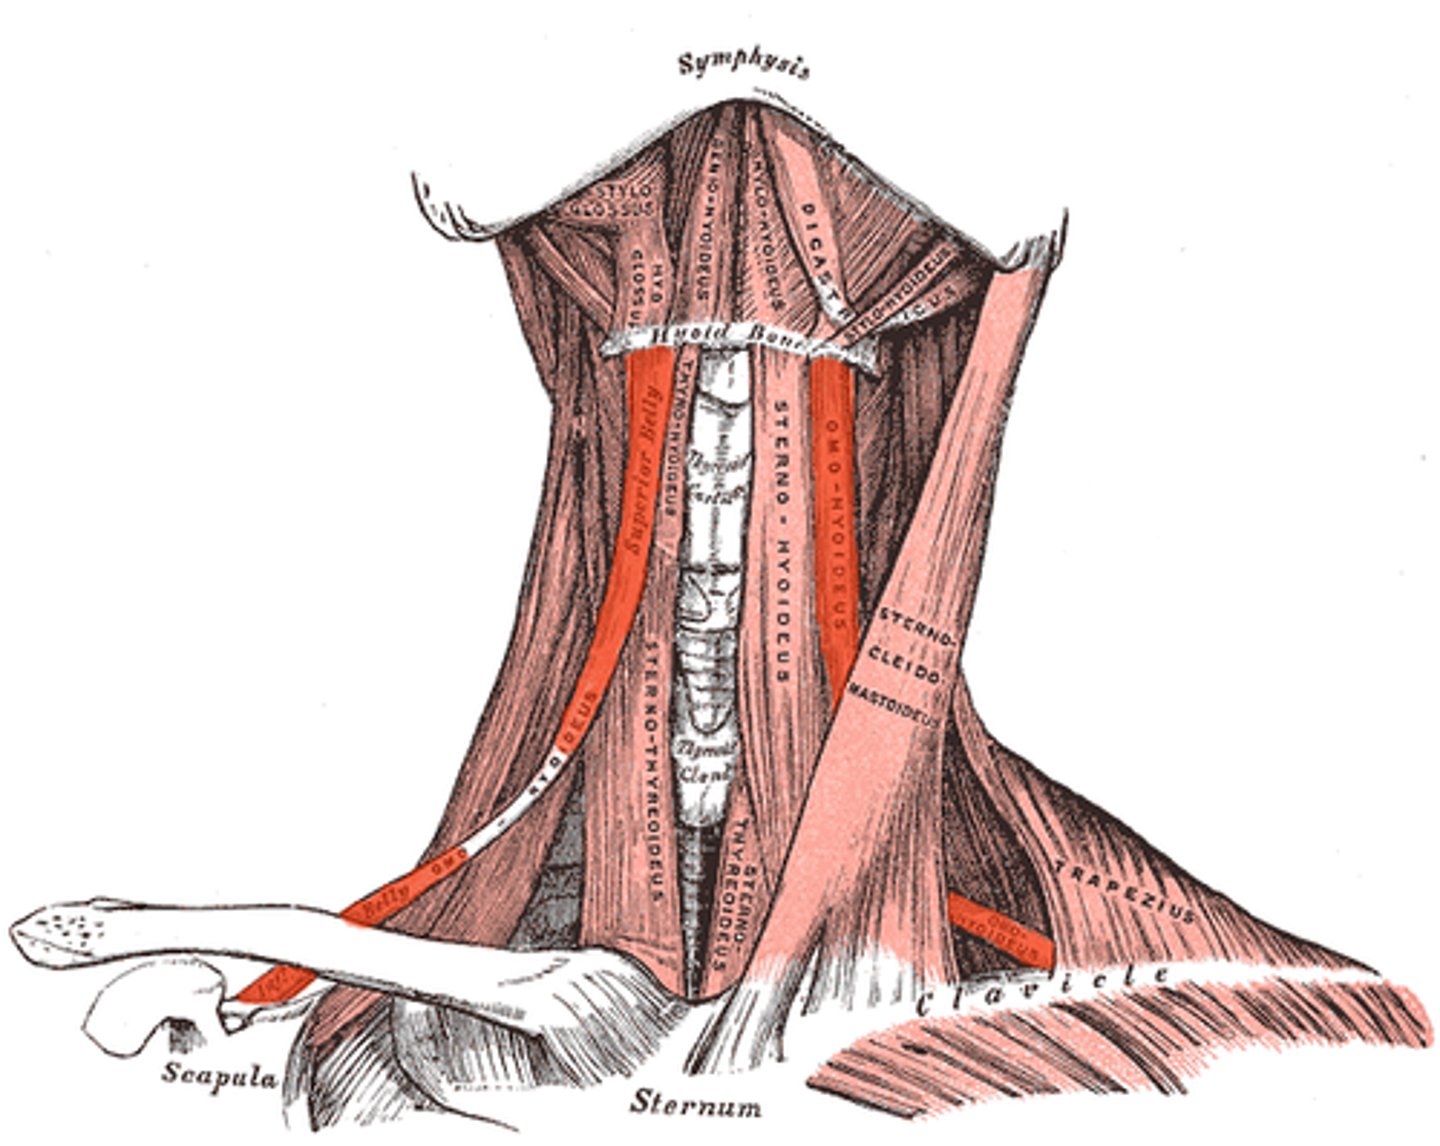

Sternohyoid m.

Origin: Clavicle/sternum

Insertion: Hyoid

Action: Depress

Omohyoid (two bellies) m.

Origin: Clavicle/scapula

Insertion: Hyoid

Action: Depress

Thyrohyoid m.

Origin: Thyroid cartilage

Insertion: Hyoid

Action: Depress, Elevate larynx

Sternothyroid m.

Origin: Sternum

Insertion: Thyroid Cartilage Action: Depress

Sternocleidomastoid m.

Origin: Sternum/Clavicle

Insertion: Mastoid Process

Action: Flex, Rotate

Trapezius m.

Origin: Occipital/vertebrae

Insertion: Spine

Action: Elevate, Depress, Adduct